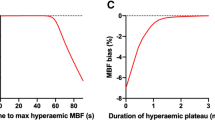

Changes in rest and adenosine stress T1 mapping

Differences in rest and adenosine stress LV myocardial T1 values between healthy controls and patients with T2DM. Scatter columns show mean LV myocardial T1 relaxation times and error bars indicate standard deviations. The lower p-values represent the differences in rest and adenosine stress LV myocardial T1, the upper p-value represent the represent the statistical difference in relative T1 reactivity between controls and patients with T2DM

There was no significant correlation between the percent change of T1 and MPRI. However, there was a significant correlation between the adenosine stress T1 and MPRI (r = 0.35, p = 0.031), when there was no significant correlation between rest T1 and MPRI (r = −0.19, p = 0.31).

Maximal T1 during adenosine stress and T1 reactivity (ΔT1) correlated negatively with LV mass index (r = −0.50, p = 0.001; r = −0.40, p = 0.018) and LV concentricity (LV mass to LV EDV ratio)(r = −0.33, p = 0.027; r = −0.41, p = 0.005) in the study group as a whole, but no significant correlation in separate groups.